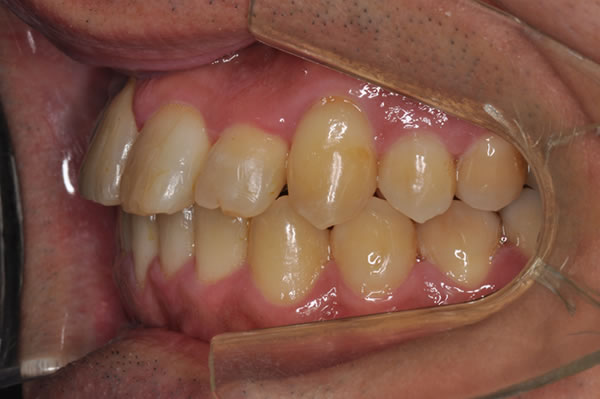

反対咬合症例

治療後